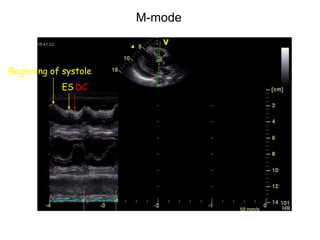

One of the earliest signs of cardiac tamponade is evidence of a

swinging heart, detected on either M-mode or two-

dimensional echocardiography - simply a marker of a large

pericardial effusion in which the four cardiac chambers are

free to float within the pericardial space in a phasic manner –

indirect evidence of elevated pressure.

 2D and M-mode

Beginning of systole

ES DC

M-mode